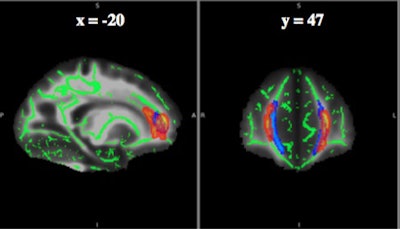

More specifically, fractional anisotropy values varied significantly in three clusters in the forceps minor and genu of the corpus callosum, based on the player's position.

Upon analysis, diffusion-tensor imaging revealed consistently lower fractional anisotropy for nonspeed players with a history of three or more concussions, compared with players with one or no concussions, in the forceps minor and genu of the corpus callosum near the frontal cortex.

DTI measures the movement of water molecules in tissue and white-matter brain regions through fractional anisotropy to determine disruptions in flow. The lower the fractional anisotropy value, the more likely there is a microstructural abnormality.

"In all three clusters, we see consistent differences in nonspeed players with a high concussion history with lower fractional anisotropy, which has been known to degrade white matter," Champagne said.

The statistical heat map for the concussion-position interaction is shown in red-orange. The major clusters were within the frontal white matter, specifically within the forceps minor (blue). This result suggests there may be a modifying effect of subconcussive impact exposure on damage to white-matter structures caused by recurrent concussions. This modifying effect appears most prominently in the frontal white-matter structures. The implications of such white-matter structural changes on late-life cognitive function are unknown. Images courtesy of Allen Champagne and Michael Clark."That led us to believe that it may be because of the impacts [nonspeed players] are receiving in the front of their helmets," Clark said. "They might not receive as many high-magnitude impacts, but they receive a lot of lower ones, which may have an effect."